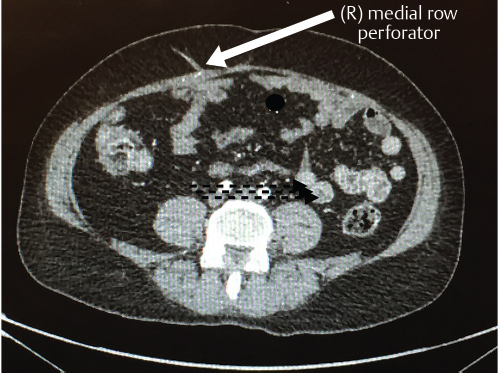

The patient stopped smoking over a 6-week period. Random cotinine testing confirmed her compliance. An MDCTA of the abdominal wall vascularity demonstrated several sizable perforators lying within the right medial rectus abdominis muscle (▶Fig. 66.7).

The patient was taken to surgery with a plan to perform an MS2-free TRAM flap, but the possibility of a DIEP flap was entertained based on the CTA results (▶Fig. 66.8a). A SPY angiogram with indocyanine green (ICG) was performed at the onset of surgery and two large perforator blooms could be seen arising from the medial row of the right rectus muscle; these were robust enough to commit to a DIEP flap instead of MS2-free TRAM (▶Fig. 66.8b,c). The flap was raised incorporating the cross midline tissue, but the tissue lateral to the left paramedian incision was discarded (▶Fig. 66.8d,e). The flap was anastomosed to the left IMA/V and the patient had an uncomplicated course apart from some minor skin necrosis of her donor site abdominal skin flap to the right of the midline. The DIEP flap healed without problems (▶Fig. 66.9).